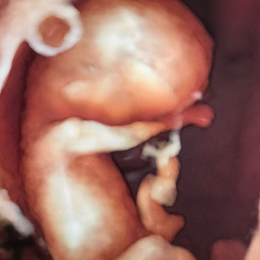

Ecografía del corazón fetal en 4D

Ocho de cada mil bebes nace con algún defecto cardíaco congénito. Estas anomalías se producen por un desarrollo anormal del corazón durante el embarazo y pueden consistir en defectos de sus paredes o válvulas, o de los vasos sanguíneos que entran o salen de él.

- Las formas nuevas de ecografía pueden proporcionar imágenes en 5-D.